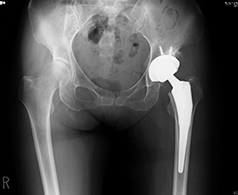

人工股関節全置換術(THA)

人工股関節全置換術とは、すり減った軟骨と痛んだ骨を取り除き、金属やプラスチックでできた人工の関節に置き換える手術です。

痛みの原因を除去できるため、確実な除痛効果が得られます。長期的にも、人工股関節全置換術施行後、10年で再置換術が必要となる確率は5%以下であり、多くの方が10年後も良好な機能を保ちつつ生活されております。

当院では、変形の程度によりますが、最小侵襲手術手技を採用し、かつ長期的な成績改善を第一優先として正確なインプラント設置を行っております。術直後の痛みは、麻酔科の協力により良好にコントロールされます。リハビリは術翌日より開始し、日常生活の復帰や社会復帰へ向け準備いたします。主な術後合併症である感染と脱臼の発生率は、一般に約1-2%と5%前後ですが、当院では現在筋肉を切らない手術(MIS)を採用しており、その率は非常に低く抑えられています。

当院で行っている最小侵襲手術(MIS)

従来、人工股関節全置換術は、15cm~20cmの皮膚切開を要し、筋肉を切開して関節に達しておりました。近年、手術手技や手術機械の飛躍的な進歩によりMIS手術が導入され、10cm~12cmの皮膚切開で、かつ筋肉同士の間からアプローチするため筋肉をほぼ切らずに従来と同等の人工股関節置換術が可能となりました。当院では十分にトレーニングを積んだ専門医が適応を十分に判断した上で、積極的にMIS手術を取り入れており、術後早期の回復及び脱臼率の低下などの成果が上がっています。